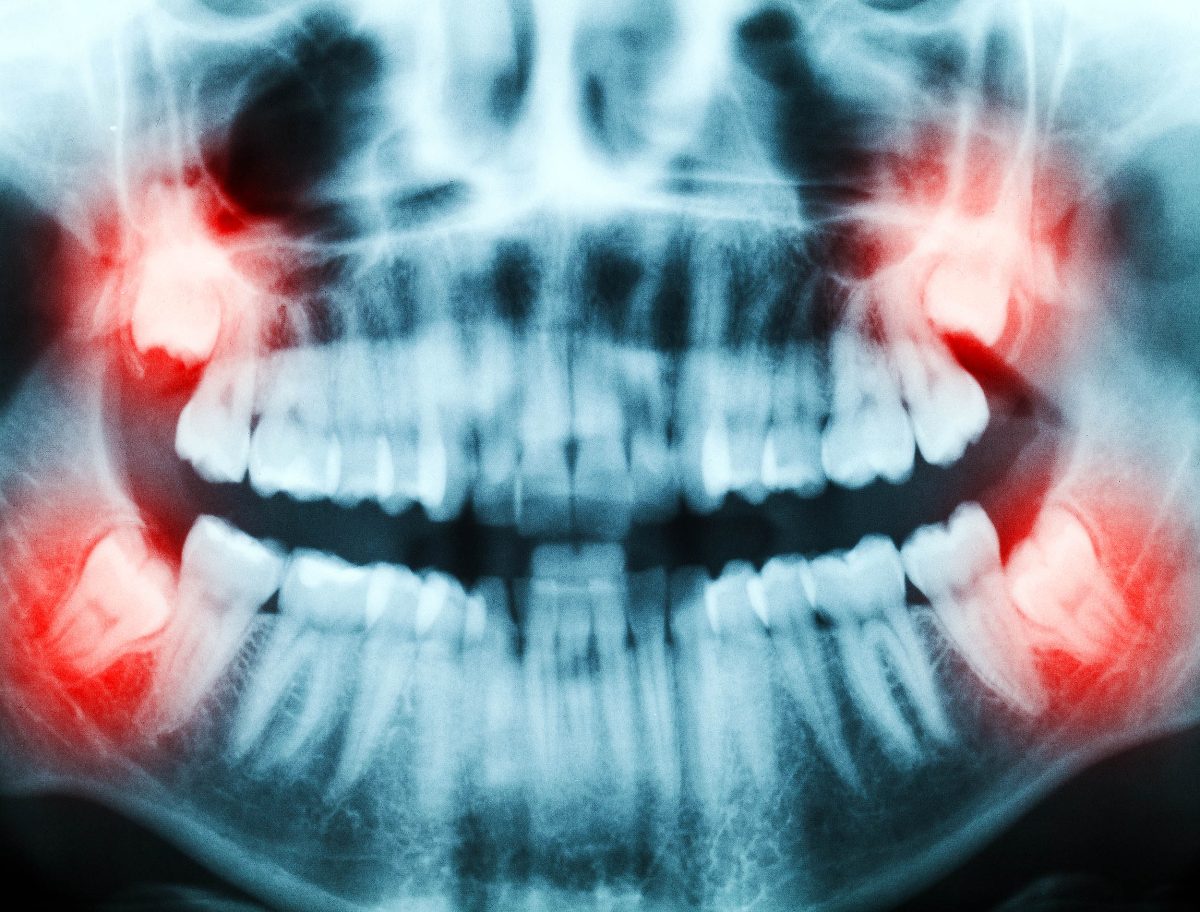

In the U.S., about 10 million wisdom teeth are extracted annually. Most of these teeth go straight to biomedical waste, but each tooth removed represents a painless source of live tissue.

Typically, dentists operate on teenagers or young adults when the pulp cells are still actively dividing and have fewer DNA errors.